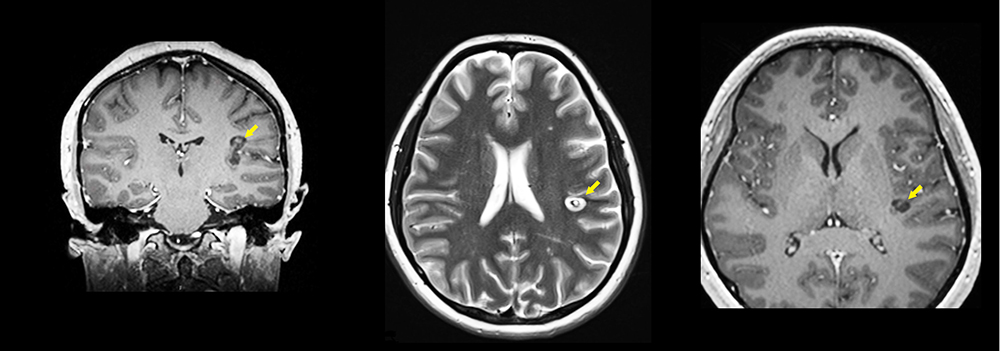

MRI showing laser ablation at area of seizure activity

Figure 2: This image was obtained during the patient’s MRI-guided surgery. The dark line in the brain is the laser catheter extending into the brain through a small opening in the skull. The marigold areas in the brain represent the area of the laser ablation at the locus of seizure activity.

Anna’s LITT took place in the intra-operative scanner on the 5th floor of The Clifton Center for Medical Breakthroughs. Anna was placed in the scanner under general anesthesia. A laser probe was inserted into the insula on the left through a pinhole incision in the scalp and a small 4.5 mm hole in the skull. The location of the laser was confirmed in real-time using the MRI scanner. The MRI was then used to monitor brain tissue temperature as the laser was turned, providing real-time information on the extent of brain tissue that had been ablated (Figure 2).